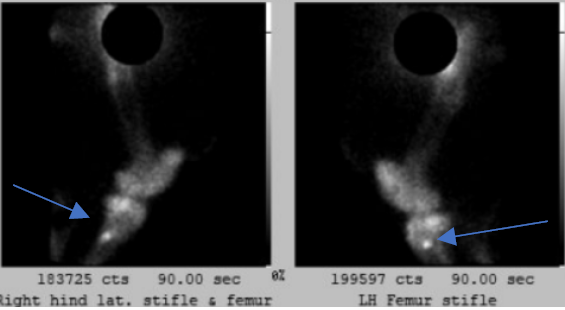

Nuclear scintigraphy is often used in non-specific lameness cases like Polly. The horse is given a radioactive isotope, T99M, via a catheter, and a large camera is used to identify areas of increased pharmaceutical uptake or ‘hot spots’. ‘Hot spots’ are indicative of increased bony turn over which, in most cases, are areas of abnormal bony change.

In Polly’s case, a full body bone scan was performed and identified marked, focal regions of increased radiopharmaceutical uptakes in the tibia and the radius. This is a highly unusual finding, but our specialist team of sports medicine vets efficiently diagnosed Polly with enostosis-like lesions or ‘bone islands’. Bone islands are defined as single or multiple regions of new bone in the medulla of long bones near nutrient foramens and are highly uncommon; The exact cause of this phenomenon is unknown but it can affect many bones simultaneously.